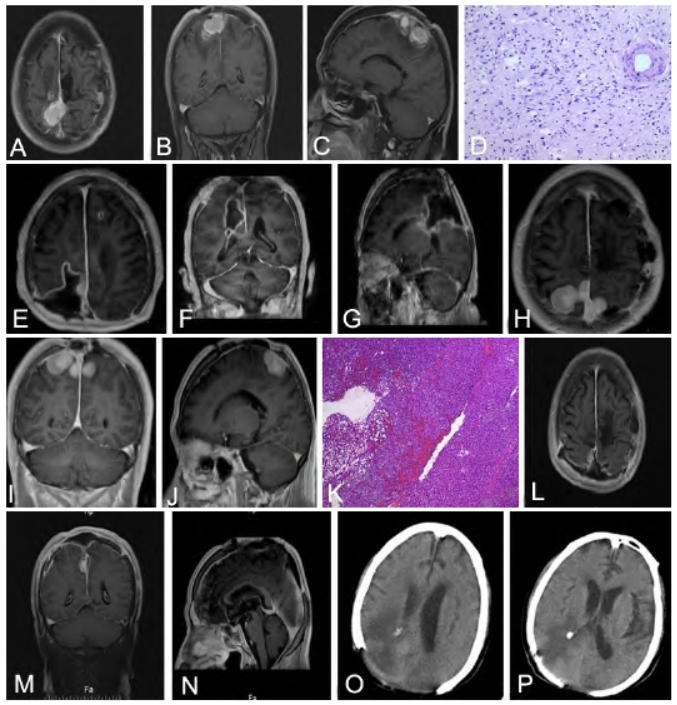

4年前,在外院曾行矢状窦旁占位病变切除术,术后病理不详。2年前,我院复查MRI示顶叶见团片样稍长T1、稍长T2信号,边缘见条状短T1信号,较大截面约1.9 cm×2.7 cm×2.7 cm,周围见大片水肿

,增强后呈均匀性强化;左顶叶见斑片样长T1、长T2信号,增强后未见明强化(图1A~C)。

因顶叶占位合并病灶内少量出血,行开颅手术治疗,术中见矢状窦处肿瘤突破硬膜破溃而出,肿瘤呈灰白色,质地硬,与周围组织界限尚清,矢状窦内部分肿瘤坏死钙化考虑肿瘤复发,术后病理示SFT(图1D),部分区伴去分化;免疫组化显示瘤细胞CD34(+)、STAT6(+)、CD99(+)、Bcl-2(+)、EMA(-)、PR(-)、GFAP(-)、S-100(-)、Calponin(-)、TLE1(-)、Ki-67(阳性率约40%)。术后复查MRI显示顶叶肿瘤切除术后改变,形成残腔(图1E~G)。

术后症状改善,无并发症,未进行放化疗。此次入院后,完善头部MRI检查显示右侧顶叶及上矢状窦区占位较前增大,顶叶及矢状窦见多发团片样稍长T1、稍长T2信号,部分相互融合,最大横截面大小约2. 5 cm×2.3 cm,周围见大片水肿,增强后呈明显均匀化(图1H~J)。

术后病理结果:(顶叶肿瘤)梭形细胞瘤,部分区瘤细胞丰富,轻-中度异型,结合组织学形态及免疫表型,考虑恶性型SFT(图1K);免疫组化显示PCK(-)、Vimentin(+)、PR(-)、EIA(-)、S-100(-)、STA(-)-STAT6(+)、CD34(+)、ERG(+)、Desmin(-)、GFAP(-)、Ki-67(热点区阳性率约为40%)。术后1个月复查MRI 双侧顶后叶以及上矢状窦区肿瘤组织较前大部分切除,部分异常强化,不排除残留或复发可能(图1L~N)。行放化疗等综合治疗。术后9个月,复查头部CT未见肿瘤复发(图1O、1P);患者双侧下肢肌力4级,麻木感改善。

图1 矢状窦旁孤立性纤维瘤多次复发并恶变患者手术前后影像及术后病理表现。A~C. 再次术前MRI显示左侧顶叶团片样稍长T1、稍长T2信号,较大截面约1.9 cm×2.7 cm×2.7 cm,周围伴大片水肿,增强后呈均匀性强化,左侧顶叶斑片样长T1、长T2信号,增强后未见明强化;D. 再次术后病理显示孤立性纤维性肿瘤(HE,×100);E~G. 再次术后复查MRI显示顶叶肿瘤切除术后改变,残腔形成;H~J. 再次术后2年MRI检查显示顶叶及矢状窦多发团片样稍长T1、稍长T2信号,部分相互融合,最大横截面大小约2.5 cm×2.3 cm,周围伴大片水肿,增强后呈明显均匀化;K. 三次术后病理显示恶性型孤立性纤维性肿瘤(HE,×40);L~N. 三次术后1个月复查MRI显示双侧顶后叶以及上矢状窦区肿瘤组织较前大部分切除,部分异常强化,不排除残留或复发可能;O、P. 三次术后9个月复查头部CT未见肿瘤复发